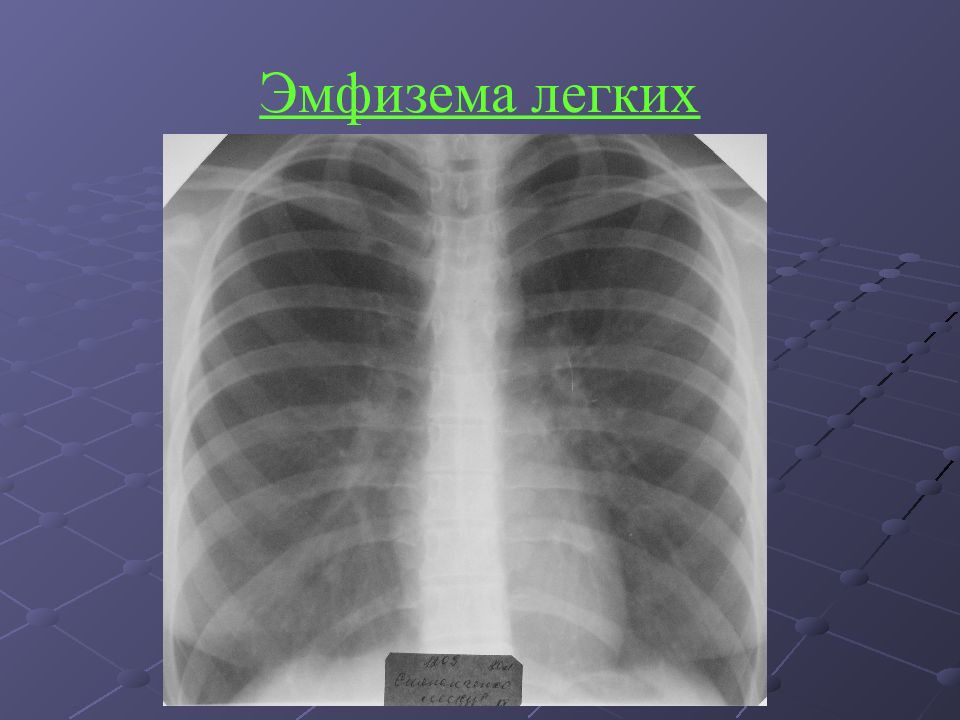

Рентгеновские снимки при врожденной эмфиземе легкого

Раздел: Визуальные уроки